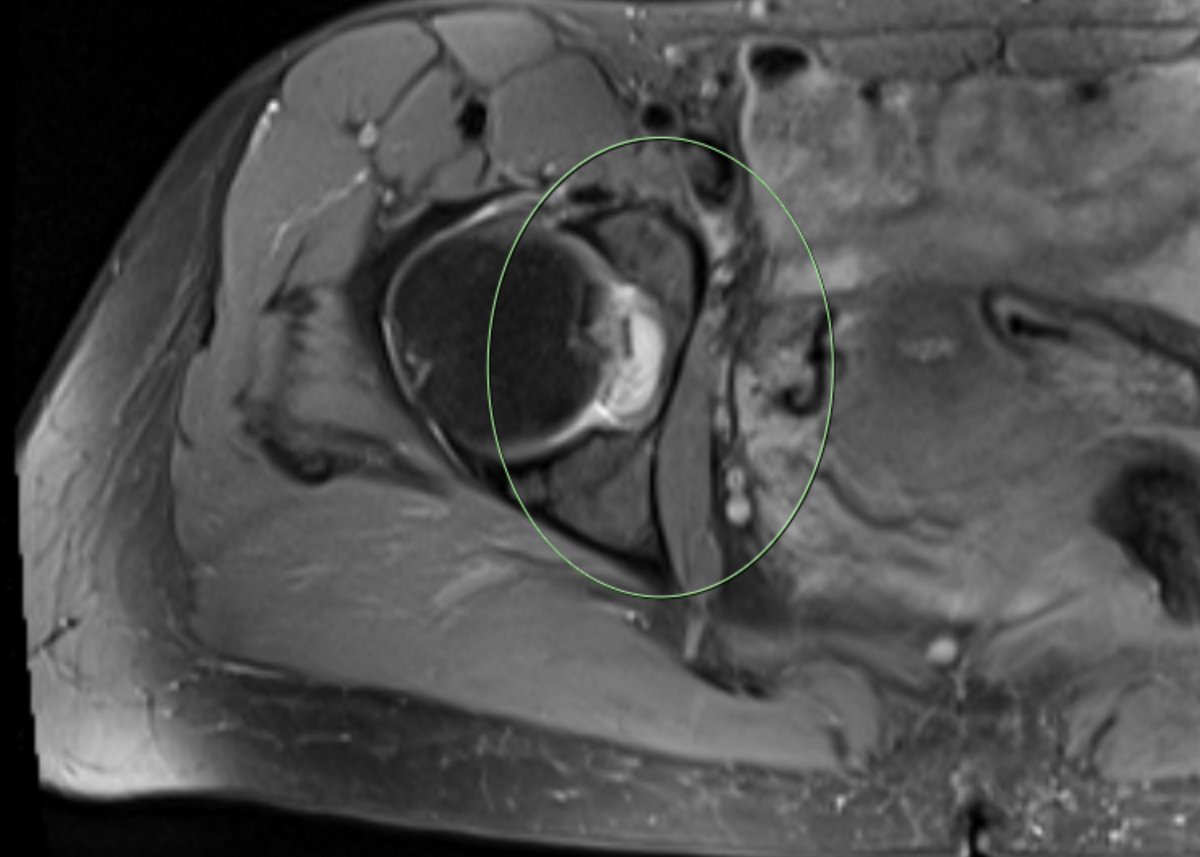

#CaseOfTheWeek‼️🥳‼️ ☢️🩻☠️Case#22☠️🩻☢️ #Mass 📲➡️➡️#Diagnosis❔❓❔ #FOAMRad #RadEd #MedEd #OrthoEd #OrthoTwitter @ssr_rwg @UWRadRes @ISSVA_org